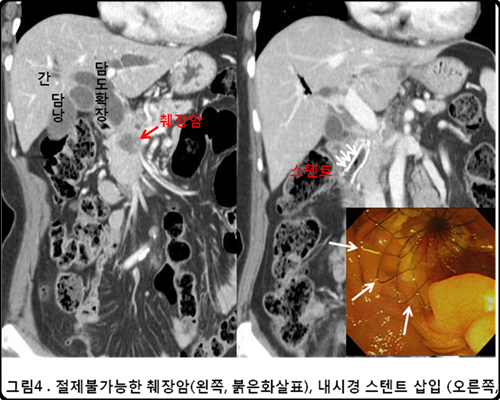

췌장은 소화효소와 인슐린, 글루카곤 등의 호르몬을 분비 및 담당하는 역할을 주로 담당합니다. 그런데 췌장에 종양이 발생하면 췌장암이라고 해요. 췌장암의 경우 사망 확률이 높은 암이라서 조기발견이 무척 중요하더라고요. 다른 질병과 증상이 비슷하며 발견될 때에는 이미 전이가 상당히 진행되는 만큼 조기발견이 힘든 암이기도 해요. 췌장암 초기증상 및 췌장암 등통증 부위에 대해 알아볼게요.

환자의 약 90%가 암 진행이 많이 진행된 상태로 암이라는 것을 발견하게 되고 때문에 치료가 쉽지 않은 암 중 하나입니다. 이러한 췌장암의 초기 증상을 살펴보도록 하겠습니다.

췌장암에 걸리는 이유는 특이한 까닭은 드러나지 않았습니다. 췌장암의 위험 인자로서 흡연, 만성 췌장암, 고칼로리의 식사, 유전 등을 들 수 있다고 합니다. 췌장암은 주로 50세 이상의 노인 남성이 주로 병이 발생한다고 해요. 초기 증상이 대다수 없으며 조기 발견율이 10% 이하로 무척 낮다고 하더라고요.